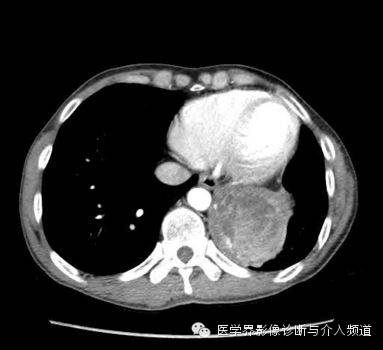

胸片示左下胸腔一肿块影。CT增强示左肺下叶一低密度肿块,其内可见高密度影,PET-CT示肿块边缘FDG摄取增加,肿块中央摄取减低。

异物性肉芽肿是纱布在人体内出现周围肉芽组织增生、纤维化时所形成的肿块,CT 表现为不均匀混杂密度软组织影,壁较厚,增强后壁由于含大量纤维结缔组织而呈明显强化,其内容物无强化。

异物性囊肿或脓肿是由于纱布引起的周围组织 、器官的慢性炎性反应,出现渗出、液化坏死并纤维包裹所形成的囊肿或脓肿,周围有假性纤维包膜或较厚的壁,CT 表现为囊性为主的混杂密度块影,壁较光滑,其内出现云雾状、漩涡状或脑回状密度增高影漂浮于其中,增强后亦表现为壁强化,内容物无强化。部分学者报道,纱布瘤内部出现气泡及边缘出现钙化是其重要特征之一。

综上所述,发生于胸腔或腹腔的肿块,具有良性病变的实性或囊性占位特征,肿块内部可见云雾状或漩涡状稍高密度影,可以出现边缘钙化,增强后壁强化,内容物无强化,再结合患者既往有手术病史,应首先考虑腹腔或胸腔纱布瘤。